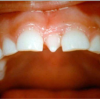

Diasteem

Diasteem – vahe esimeste hammaste vahel. Esineb 50%-l 6-8 aastastel lastel. Kuni 2 mm diasteemi puhul on, peale lateraalse intsisiivi ja silmahamba lõikumist, võimalik diasteemi iseeneslik sulgumine. Diasteem, mille suurus...